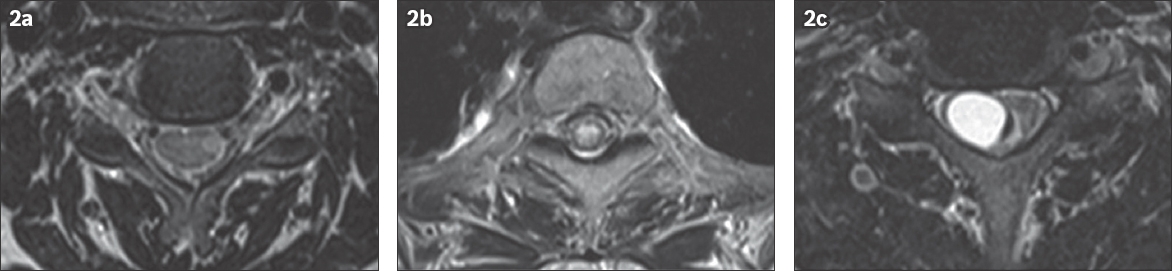

With respect to imaging, the MR findings of SCD are almost pathognomonic for this disease, with striking long-segment, symmetric and pyramidal-shaped T2 hyperintensities in the region of the dorsal columns.(10) This signal abnormality is typically nonenhancing, and creates a characteristic inverted V appearance on axial imaging. Very few disease entities will have this classic MR appearance in isolation; acquired immune deficiency syndrome-associated vacuolar myelopathy and copper deficiency are some of the few entities known to be radiologically identical to SCD.(11,12) Demyelination, infection, autoimmune processes, neoplasm and vascular entities can also mimic SCD on MR imaging, yet these processes can potentially be differentiated on close inspection.(11) A recent review of T2 hyperintense spinal cord lesions by Bou-Haidar et al provides a concise outline for their differentiation.(11) For example, demyelination from multiple sclerosis is typically asymmetrical, dorsolaterally positioned within the cord, and less than two vertebral body segments in length (

Fig. 2

(a) A 34-year-old woman presented with vague sensorimotor symptoms and was diagnosed with multiple sclerosis. Axial T2 fat saturated MR image of the cervical spine shows a laterally positioned asymmetric hyperintensity. (b) A 54-year-old woman with a known history of Sjogren’s disease complained of weakness in the lower extremities. Axial T2 MR image of the upper thoracic spine shows a centrally positioned hyperintensity involving more than two-thirds of the cord diameter. (c) A 45-year-old man presented with numbness and tingling in the extremities. Axial T2 fat saturated MR image of the cervical spine shows an expansile, eccentrically-located tumoral cyst and a small crescentic region of haemorrhage along the medial surface of the cyst. Biopsy confirmed that it was an ependymoma.